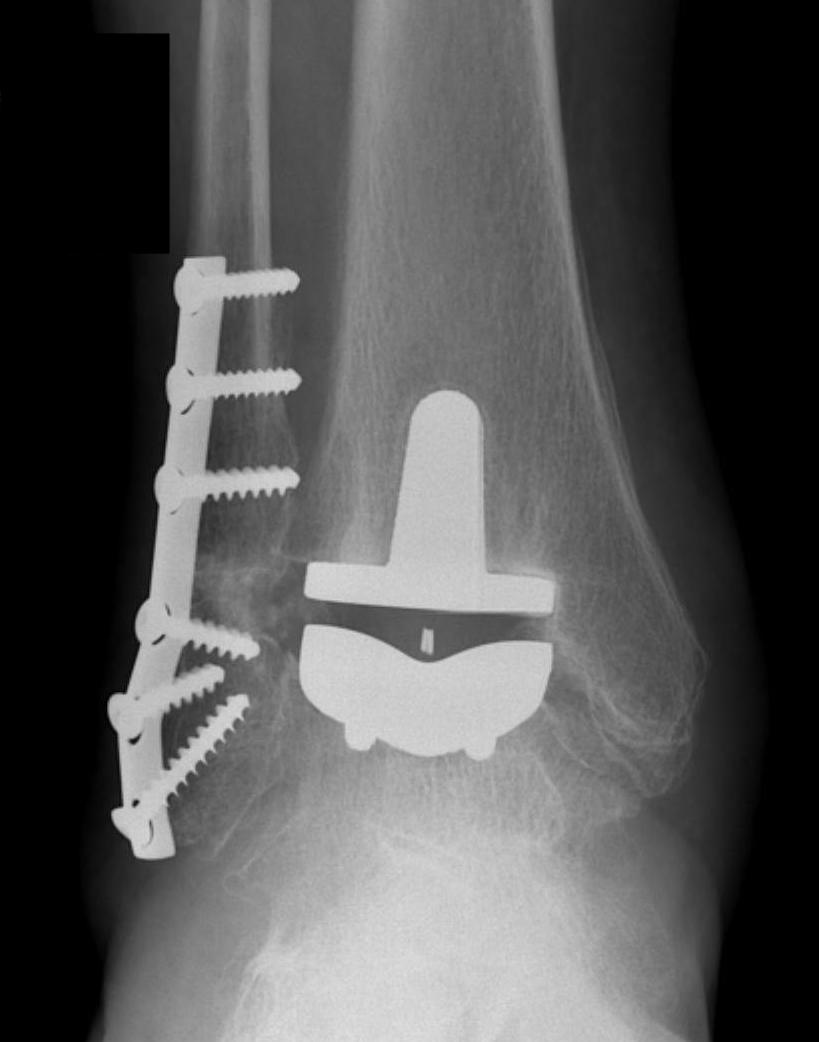

Infinity implant STAR implant Inbone

Agility Salto Tolaris Trabecular metal

Technique

A. Anterior approach

Tibial cut

- distal alignment jig / extramedullar jig +/- image intensifier +/- patient specific jigs

- resect few mm above eroded bone

- preserve medial and lateral malleolus

Talar dome resurfacing

- jig to make chamfer cuts

Insert mobile / fixed bearing